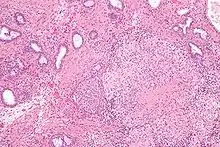

Micrograph showing granulomatous inflammation of bladder neck tissue due to Bacillus Calmette-Guérin used to treat bladder cancer, H&E stain

BCG has been one of the most successful immunotherapies.[27] BCG vaccine has been the "standard of care for patients with bladder cancer (NMIBC)" since 1977.[27][28] By 2014 there were more than eight different considered biosimilar agents or strains used for the treatment of non–muscle-invasive bladder cancer (NMIBC).[27] [28]